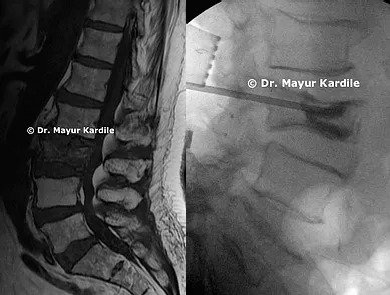

Degenerative Listhesis

65 yr gentleman